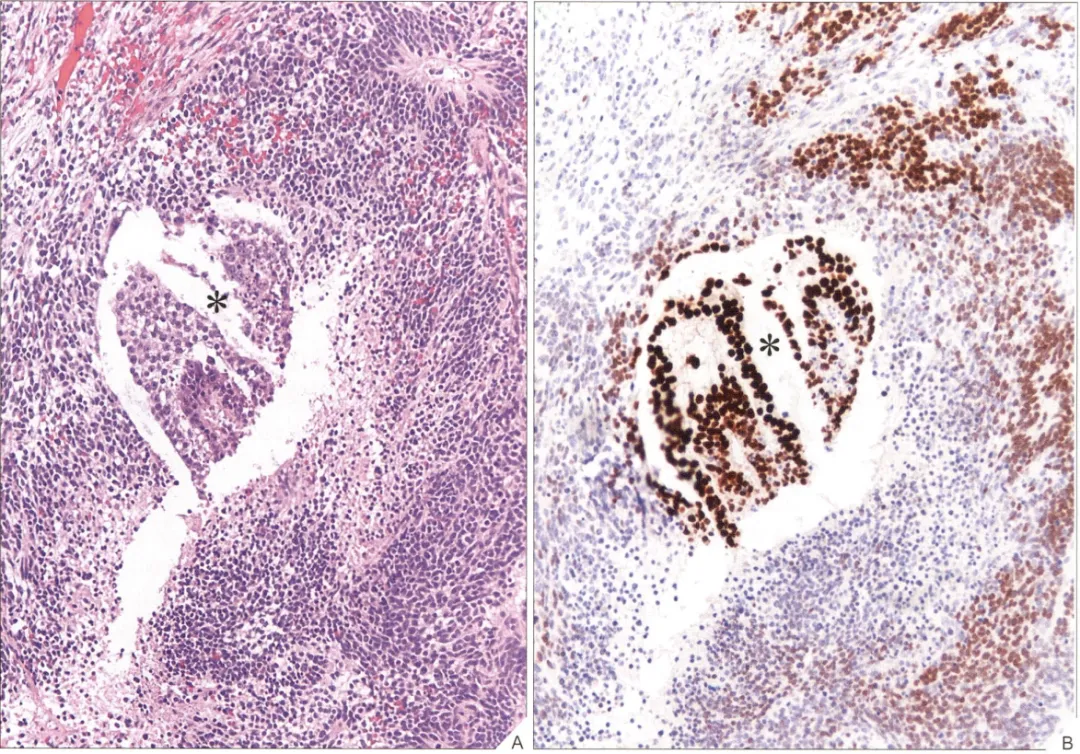

确诊未成熟性畸胎瘤核心是必须要有未成熟的神经外胚层组织,其间混以不同比例的成熟组织(图2A、B)。

内胚层成分包括肝组织、未成熟腺体(如肠型或呼吸型上皮)或成熟黏液腺体、甲状腺组织及类似Wilms瘤的胚胎性肾组织等(相对少见),需要注意的是,上述组织的单独存在不能诊断未成熟性畸胎瘤。此外未成熟性畸胎瘤也可合并卵黄囊瘤、绒毛膜癌或胚胎性癌成分,其中以卵黄囊瘤最为常见(图3),可为肿瘤的主要成分或形成小的播散性病灶,一旦发现上述成分则应诊断为“混合性生殖细胞肿瘤”。另外这些非畸胎瘤性生殖细胞肿瘤的最大线径如果不超过2mm,那么对患者的预后没有影响。

图3 未成熟畸胎瘤中的少许卵黄囊瘤成分,SALL4染色卵黄囊瘤成分呈核强阳性表达而未成熟神经组织表达相对较弱(图片来源于参考文献1)